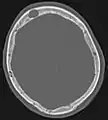

Scanner d'une métastase ostéocondensante dans l'os du crâne d'un patient souffrant d'un carcinome de la prostate. On reconnaît clairement l'extension de la métastase au-delà des limites initiales de l’os.

Par comparaison, scanner de métastases ostéolytiques dans l'os du crâne d'une patiente souffrant d'un cancer du sein. On distingue une ostéolyse plus grande sur le front, et plusieurs plus petites.